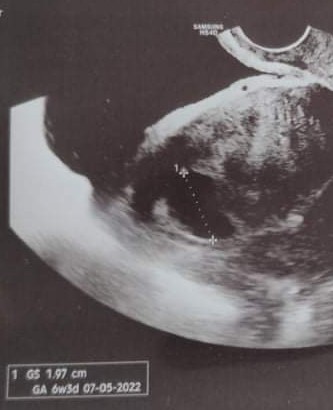

Witam, 14/09 miałam badanie USG gdzie pojawił się pusty pęcherzyk ciążowy i po zmierzeniu miał 1,97cm- wiek 6t3d. Ginekolog dała mi skierowanie na badania progesteronu i bety hcg, które zrobiłam następnego dnia. Beta wyszła dosyć duża, bo ponad 25 000 a progesteron 10,4. Jutro mam kolejne badanie krwi dla porównania bety... a w środę kolejne usg... Czy któraś z was miała podobnie i czy historia miała dobre zakończenie?

Załączniki

• received_832759157385368~2.jpeg

received_832759157385368~2.jpeg

22,8 KB · Wyświetleń: 326